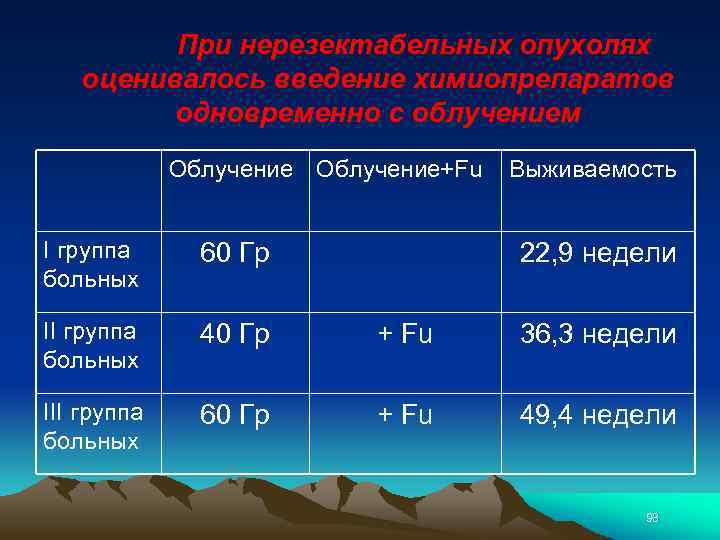

При нерезектабельных опухолях оценивалось введение химиопрепаратов одновременно с облучением Облучение+Fu Выживаемость I группа больных 60 Гр II группа больных 40 Гр + Fu 36, 3 недели III группа больных 60 Гр + Fu 49, 4 недели 22, 9 недели 98